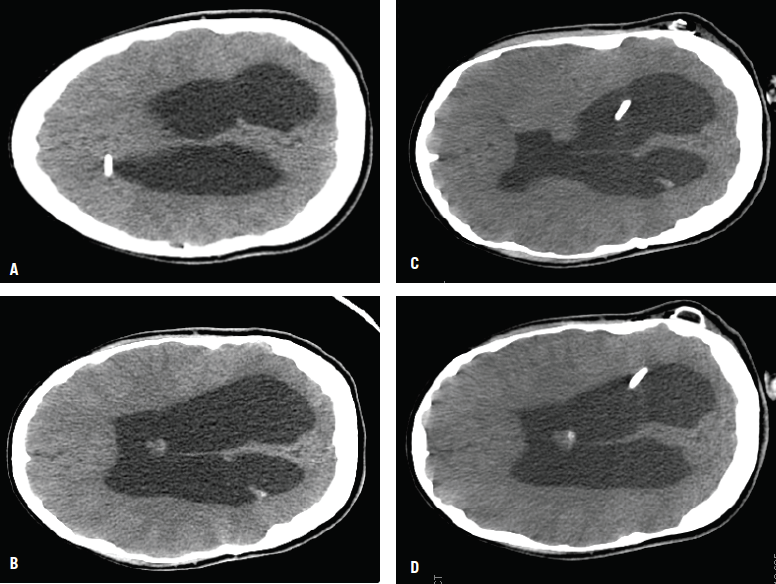

Figure - Preoperative CT scans showed the ventriculoperitoneal shunt catheter on the right side outside the ventricle (A), and an enlarged lateral ventricle with effaced sulci (B). Postoperative CT scans showed the new left ventricular catheter after the second shunt placement (C); the ventricular size (D) is similar to the preoperative size.

After her return home to the United States, a preoperative ophthalmology examination revealed bilateral optic atrophy and loss of color vision, constricted visual fields in the right eye, and the ability to count fingers only at close range in the left eye. She underwent surgical revision of the shunt; preoperative and postoperative CT images are shown in the accompanying Figure.